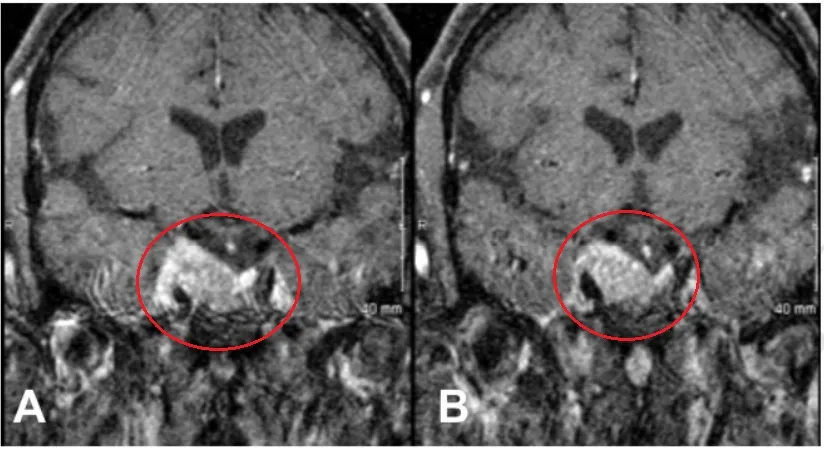

术前肿瘤持续生长进入海绵窦

INC福教授为Estelle采用标准经鼻经蝶窦入路内镜手术,随后通过移除海绵窦颈内动脉前段上的骨质进行外侧扩展术野。

内镜下经内侧三角入路

术后,Estelle动眼神经麻痹症状得到缓解,恢复过程平稳。患者维持术前药物治疗方案。病理学检查确认病变为垂体腺瘤,未见恶变特征。

经过三年随访,影像学检查未发现肿瘤复发或生长。